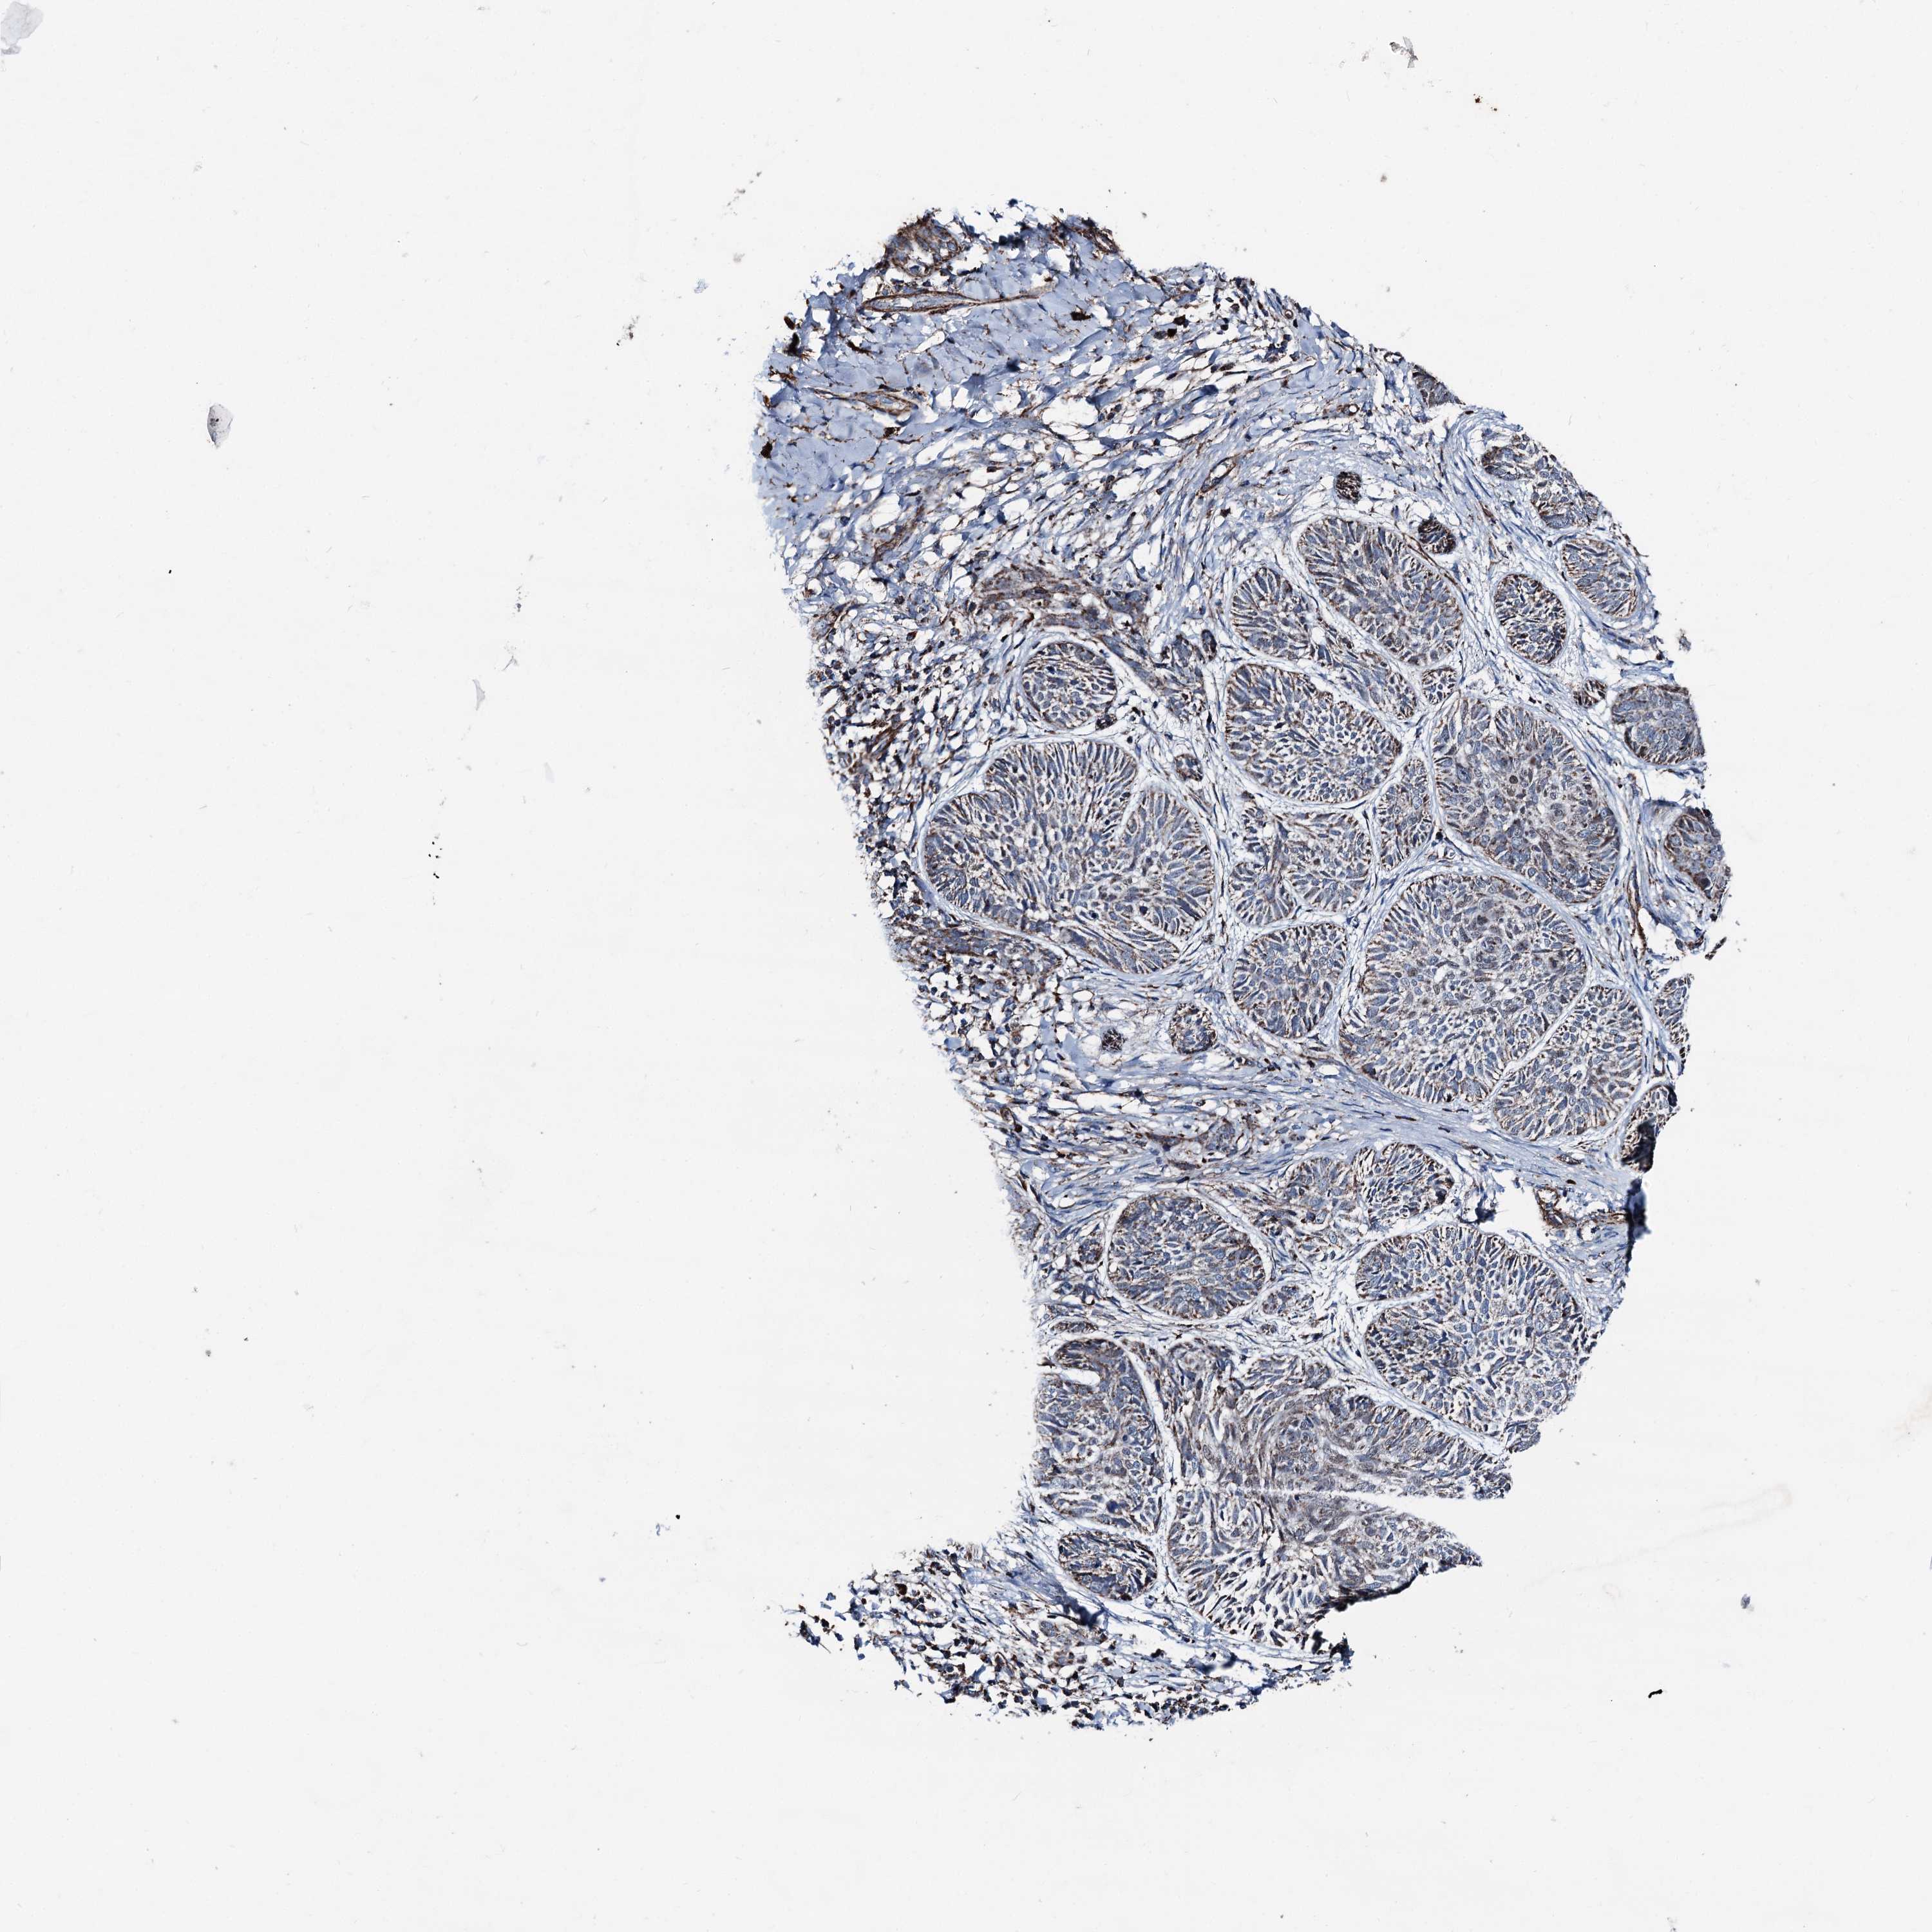

CANCER SKIN CANCER Show tissue menu

Basal cell and squamous cell cancer

SKIN CANCER - Protein expressioni

A mouse-over function shows sample information and annotation data. Click on an image to view it in a full screen mode. Samples can be filtered based on level of antibody staining by selecting one or several of the following categories: high, medium, low and not detected. The assay and annotation is described here.

Each image is clickable and will lead to virtual microscopy that enables deeper exploration of all samples and also displays staining intensity scores, fraction scores and subcellular localization as well as patient and tissue information for each sample.

Antibody HPA038540

Basal cell carcinoma

Squamous cell carcinoma, NOS

Squamous cell carcinoma, metastatic, NOS